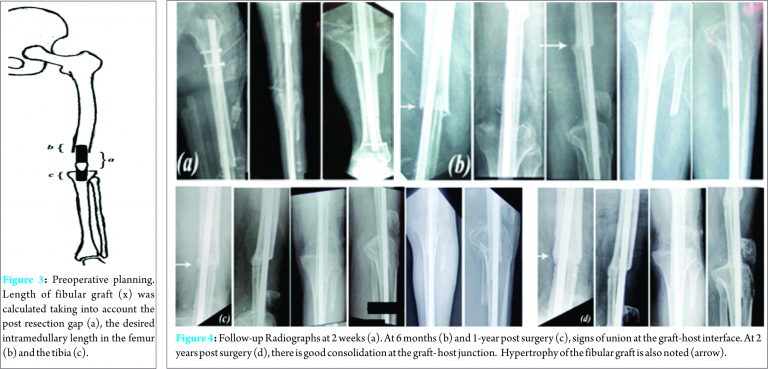

The desired length of the fibular graft (x) was estimated using the calculation (Fig. 3):

x = a + b + c ; where a was the estimated bone gap; b was the length of the fibula to sink intramedullary into the femur. c was the lntramedullary sink of the fibula in the proximal tibia.

Length of the fibular graft was calculated to 11.5 cms (x= 10 + 0.5 + 1). “b” was estimated to be 0.5 cms since the fibular graft was to be inserted into the narrow medullary canal of the femoral diaphysis. “c” was estimated to be 1cm since the fibula was to be inserted into the broad metaphyseal region of the proximal tibia. The desired length of the limb was calculated to allow for post arthrodesis limb clearance and final graft length was estimated by subtracting the desired limb shortening from the graft length. Final length of the graft (y) in situ was calculated to 9.5cms, (y = x-2 ie 11.5-2 = 9.5 cms) A fibula graft of approximately 12 cms was harvested from both the legs using the postero-lateral approach, was fashioned to the calculated length and tied to a custom-made intramedullary interlock nail using a no.1 Polyglactin 910 suture and was inserted from the piriformis fossa extending up to the distal metaphysis of the tibia. Thereby, an intramedullary bone grafting was done with the dual fibular graft spanning over the defects with the grafts wedged proximally and distally in the medullary canal of the femur and tibia to achieve the desired limb length. Interlocking was performed under fluoroscopic guidance. Suture removal was done at 2 weeks post surgery and there were no post-operative wound complications. The limb shortening was 2 cms post-operatively.

A variety of treatment modalities are available for a GCT, which include curettage and application of cryotherapy or phenol along with bone grafting or implantation of bone cement (methylmethacrylate or hydroxyapatite). Wide local resection followed by allograft or prosthetic reconstruction can also be done. Intralesional curettage is a standard treatment for giant cell tumours (GCT) of long bones, with or without the use of polymethylmethacrylate (PMMA). This however, is associated with high risk of recurrences as compared to wide local resection.[1, 5 – 9] The autologous fibula graft is commonly used for reconstruction of the upper and lower limbs post tumor resection. The choice of graft varies from unilateral vascularized or non- vascularized fibular graft; a mantle fibular graft, which essentially is a combination of an allograft and an autologous graft [10] or a bilateral fibular graft. Massive allografts have high rates of complications like nonunion and infection. Also, the immediate postoperative course involves long periods of none or partial weight-bearing of the affected limb, leading to complications like muscular insufficiency, demineralization of the native or grafted bone and pathological fractures [11,12]. The advantage of bilateral fibular grafts in long bone reconstructions is that the autologous transplant provides excellent chances for remodeling at the recipient site and shows good results with lesser complications particularly in the reconstruction of femoral defects. [13] Also, being a simpler procedure, it reduces the surgical time and need for microsurgical setup thereby being cost effective. For reconstruction of femoral defect, a bilateral free fibular graft can increase the primary stability and weight bearing can be accelerated. Internal fixation is generally preferred since implant removal is not required [14] and patients may receive postoperative chemotherapy, thereby reducing the risk of infection during times of pancytopenia. [15] Weight bearing is increased individually according to osseous integration of the fibular graft. Our patient was kept Non-weight bearing for the first 3 months and was started on partial weight bearing subsequently. Full weight bearing was initiated at 8 months, as was suggested by previous studies [16,17]. Follow-up radiographs (Fig. 4) indicated signs of union and no signs of graft resorption or infection. At 2 years post surgery, the patient was walking Full- weight bearing with a shortening of 2 cms, a healthy scar and no evidence of a recurrence. X-rays (Fig. 4 [d]) revealed consolidation of the graft and union at the graft-host junction. Hypertrophy of the fibular graft was also noted in comparison to the immediate post -operative radiographs.